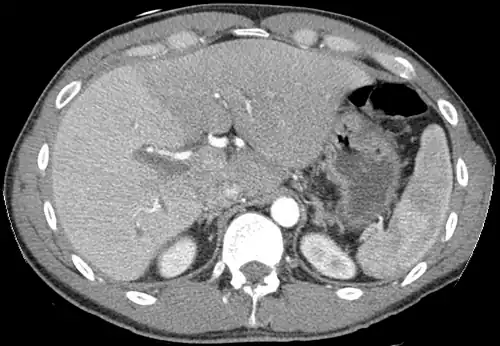

The diagnosis of liver disease is made by liver function tests, groups of blood tests, that can readily show the extent of liver damage. If infection is suspected, then other serological tests will be carried out. A physical examination of the liver can only reveal its size and any tenderness, and some form of imaging such as an ultrasound or CT scan may also be needed.

- Axial CT image showing anomalous hepatic veins coursing on the liver's subcapsular anterior surface[74]

- A CT scan in which the liver and portal vein are shown